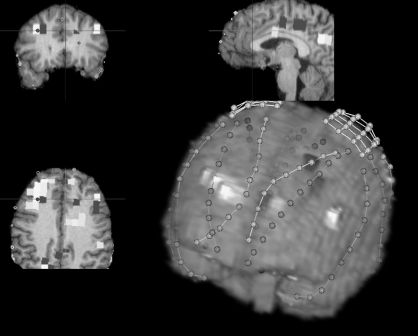

Currently, the [ldquo]gold standard[rdquo] for the localization of seizures in intractable cases of epilepsy is intracranial electroencephalography (icEEG). Though highly effective, icEEG requires that electrode leads be surgically implanted, and the cost and complexity associated with this procedure presents a barrier to treatment that might be mitigated by less expensive and invasive methods. Magnetic resonance spectroscopic imaging (MRSI) is a new, noninvasive tool that has proven to be effective for lateralizing seizures in temporal lobe epilepsy. The goal of this study is to establish correlation between the results of traditional icEEG methods and measurements obtained using proton (1H) MRSI. We identified 9 patients with intractable epilepsy who had 1H-MRSI taken prior to intracranial electrode implantation. Single and multislice 1H MRSI was performed on a 4 Tesla Varian MR system. Data was obtained using a previously published pulse sequence with 8mm x 8mm x 10mm resolution. For each spectroscopy voxel, we calculated the difference between the measured ratio of creatine to N-acetyl-aspartate and an expected ratio based on the grey matter content of that voxel in a group of normal controls. These values were used to determine lateralization of seizures.Subsequently, the patients underwent intracranial electroencephalography and seizure localization and lateralization was determined by ictal EEG recordings. The intracranial EEG electrode locations were co-registered with the MRSI data using software developed at Yale. For each patient, we compared the clinical lateralization made using icEEG methods with MRSI lateralization results. The figure demonstrates the co-registration of MRSI, MRI and intracranial electrodes on a subject. Voxels where the NAA/Cr ratio on MRS was significantly different from controls are highlighted. We found that icEEG and MRSI lateralization was concordant in all 9 subjects. It is apparent from these results that MRSI is a reliable method of lateralizing seizures. MRSI is capable of much higher spatial resolution. Further analysis correlating quantitative measures of icEEG with MRSI data on a voxel by voxel basis are underway. These studies are needed to determine whether noninvasive MRSI can be used to localize seizures more precisely.[figure1] (Supported by NIH - NINDS and R01EB000473.)